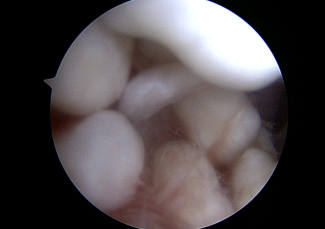

Synovial Chondromatosis of the Elbow

The patient is a 40 year old recreational athlete who presents with catching, locking, and swelling to his elbow. He has also experienced a loss of motion gradually over the last few years. MRI (photo 1,2,3) demonstrates loose bodies that were “too numerous too count” according to the radiologist’s report and consistent with the diagnosis of synovial chondromatosis – a benign condition. The patient underwent arthroscopic surgery of the elbow and the numerous loose bodies were seen and removed (Photo 4,5,6). The pieces ranged in size from that of a grain of a rice to a pea (Photo 7,8). The patient returned to cross fit and his regular workout regime within 6 weeks.